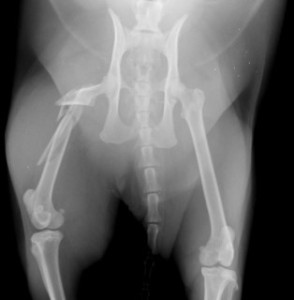

手術前

手術後

ロッキングプレートで整復しました。